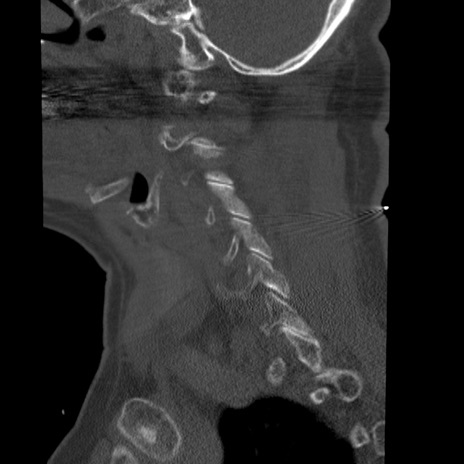

症例50 頚椎CT(矢状断像)

【症例】60歳代女性

【主訴】後頭部〜右後頸部にかけての痛み

【現病歴】本日飲食店でコーヒーを飲んでいたところ、突然後頭部〜右後頸部にかけて痛みが出現し、右上肢の感覚障害を伴ったため救急要請。

【身体所見】脳神経学的に明らかな異常所見を認めず。右上肢に軽度の感覚障害あり。

異常所見と診断は?

横断像